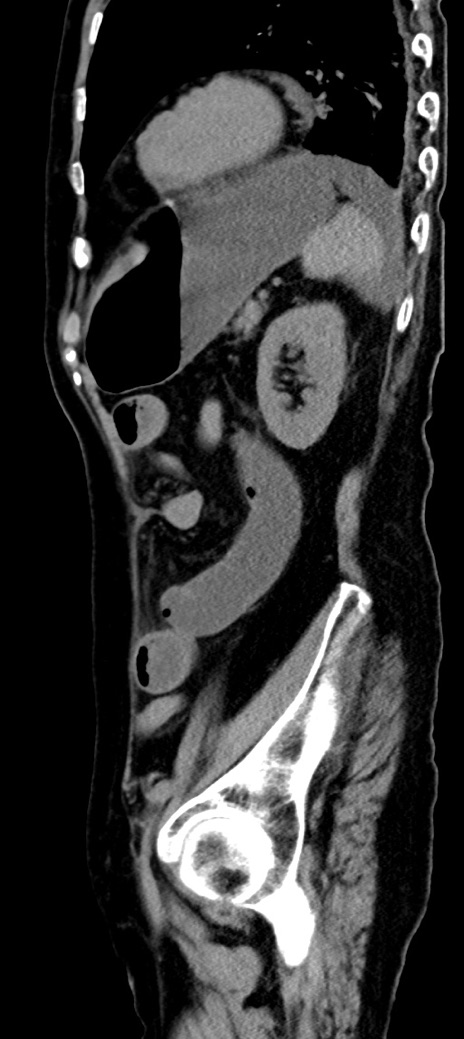

横断像

冠状断像

他院CT